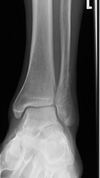

what needs to be open on an AP ankle

A

medial mortise

tibiotalar js

error

external rotation

15

Q

internal rotation